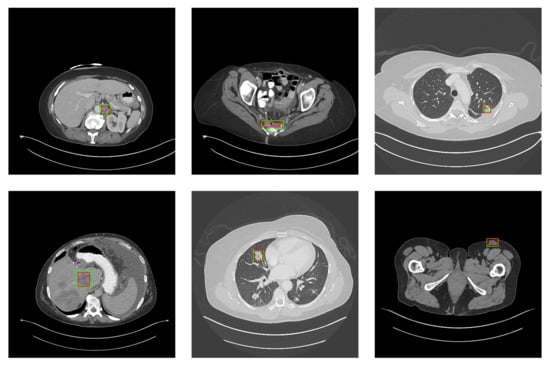

5.2. Detection Results

For further comparison, we extracted six images from the CT image series of DeepLesion. These images were taken from different sites of lesions and different areas of lesions, showing the detection results of the comparison model as comprehensively as possible. Figure 10, Figure 11, Figure 12, Figure 13, Figure 14, Figure 15, Figure 16, Figure 17, Figure 18 and Figure 19 show the detection results. All green boxes represent ground truth; red boxes denote predicted bounding boxes. It can be seen that Faster-RCNN performs very poorly on small lesions and lesions that are not easy to identify, while YOLO v3, YOLO v4, and SSD series perform relatively well. However, the aspect regression of the bounding box at small lesion locations is still not accurate. On the other hand, EfficientDet, Mask-RCNN, and YOLO v5 perform relatively well and detect lesions accurately. This may be related to the attention extraction module in these networks.

Figure 10.

The detection results of YOLO v3 in the DeepLesion dataset. The green box marks the location of the lesion.

Figure 11.

The detection results of YOLO v4 in the DeepLesion dataset. The green box marks the location of the lesion.

Figure 12.

The detection results of YOLO v5 in the DeepLesion dataset. The green box marks the location of the lesion.

Figure 13.

The detection results of Faster-RCNN in the DeepLesion dataset. The green box marks the location of the lesion.

Figure 14.

The detection results of Mask-RCNN in the DeepLesion dataset. The green box marks the location of the lesion.

Figure 15.

The detection results of EfficientDet in the DeepLesion dataset. The green box marks the location of the lesion.

Figure 16.

The detection results of SSD 300 in the DeepLesion dataset. The green box marks the location of the lesion.

Figure 17.

The detection results of SSD 512 in the DeepLesion dataset. The green box marks the location of the lesion.

Figure 18.

The detection results of SGDN 300 in the DeepLesion dataset. The green box marks the location of the lesion.

Figure 19.

The detection results of SGDN 512 in the DeepLesion dataset. The green box marks the location of the lesion.

Our model, especially SGDN 512, outperforms the previous models by detecting lesions with high accuracy for non-minimal lesions. Although there is still room for improvement, it has outperformed other models. On the one hand, we augment the image with the GAN model before it is fed into the backbone. On the other hand, we add the GAN model to the attention extraction module of the model, which can significantly improve the model’s robustness.

According to Figure 10, Figure 11, Figure 12, Figure 13, Figure 14, Figure 15, Figure 16, Figure 17, Figure 18 and Figure 19, the proposed model produces the most comprehensive detection results compared to other models. However, there are still a few cases where the shortcomings of SGDN can be seen: the arrows in Figure 19 show that our model is still not accurate at the edge of the lesion. In addition, from these figures, we can see that all the comparison models perform very poorly at the site of arrow A. The difference between the predicted box and the ground truth given by our model at arrow A is the largest compared to other recognition results.